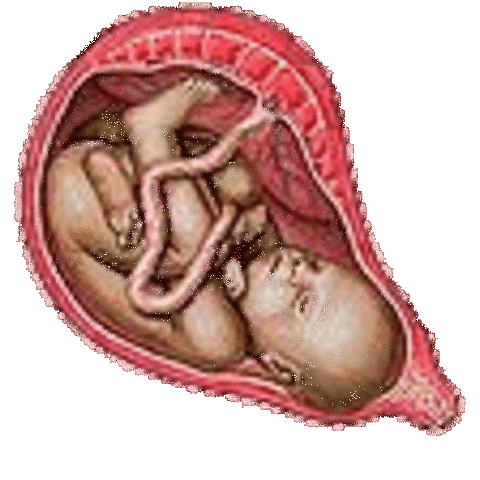

• Week Thirty Six: Baby May Drop into the Birth Canal

Week Thirty Six: Baby May Drop into the Birth Canal

Fat layers continue to build. It is possible the mother would feel contractions in the womb. The baby may also drop into the birth canal making it easier to breathe for the mother

• Week Thirty Seven: Pregnancy is Considered 'At Term'

Week Thirty Seven: Pregnancy is Considered 'At Term'

The baby is gaining one ounce a day. The water could now break at anytime.

• Week Thirty Eight: Development is Complete

Week Thirty Eight: Development is Complete